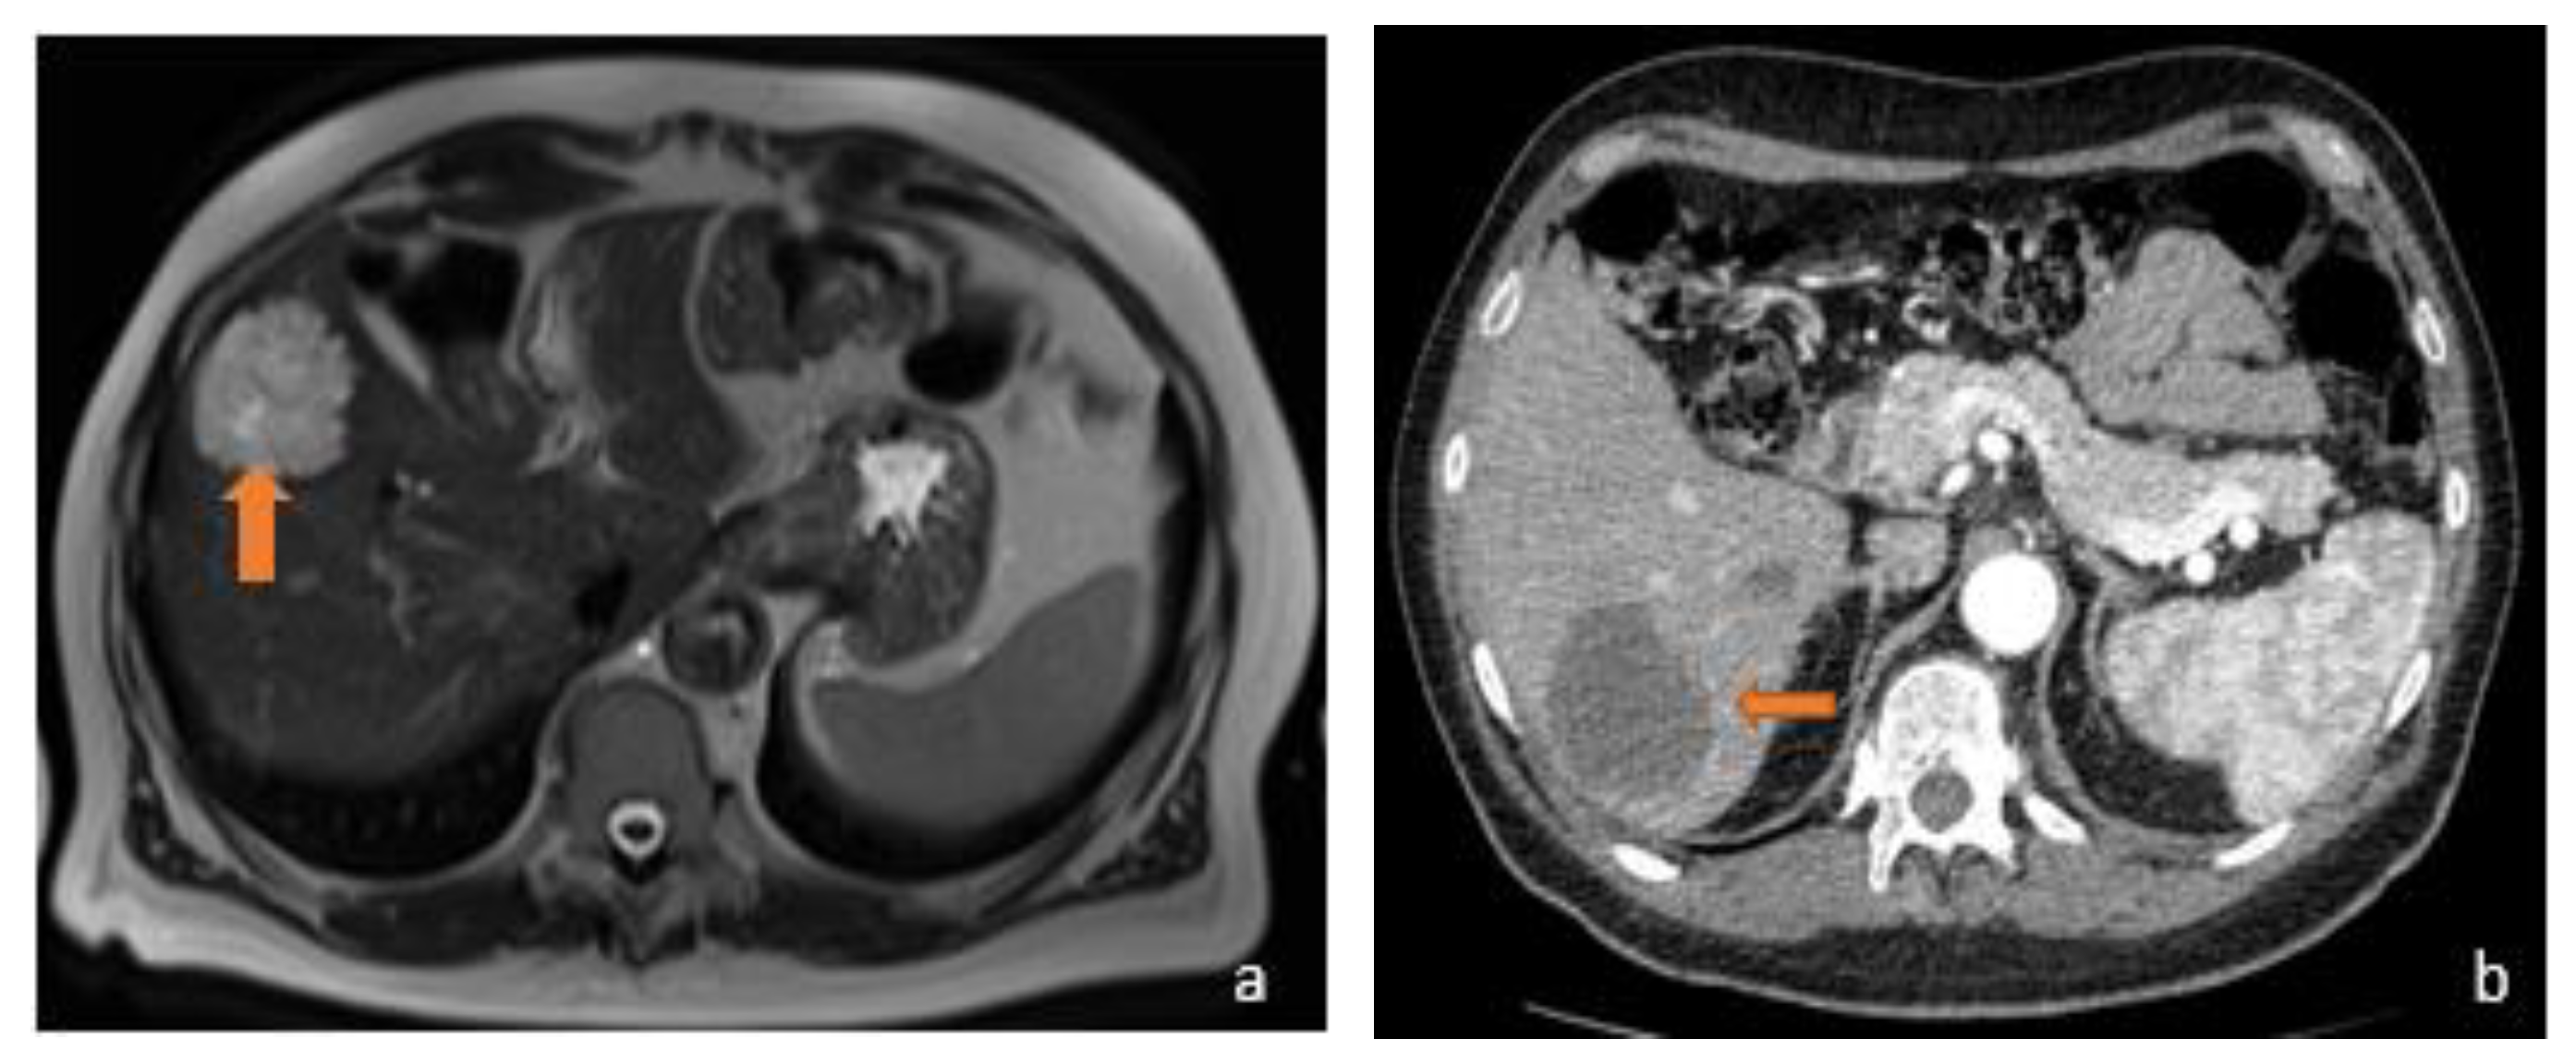

3.1. FLL Feature Characteristic

5.1. FLL Feature Characteristic